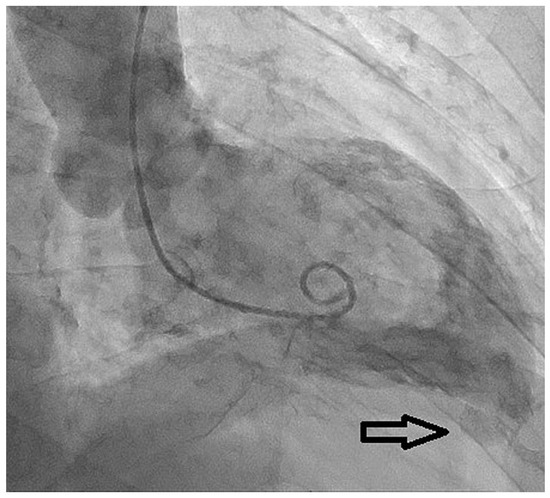

Congenital Left Ventricular Diverticulum in an Asymptomatic Patient: Multi-Modal Evaluation

by Negro Alessandro, Carballo David, Noble Stéphane and Müller Hajo

Congenital left ventricular diverticula are rare cardiac malformations. Few data are available regarding their prevalence, which is estimated to be around 0.04% and 0.7%, according to retrospective series. In our case a diverticular apical lesion of the left ventricle was incidentally found on [...] Read more.

Congenital left ventricular diverticula are rare cardiac malformations. Few data are available regarding their prevalence, which is estimated to be around 0.04% and 0.7%, according to retrospective series. In our case a diverticular apical lesion of the left ventricle was incidentally found on an urgent thoracic computed tomography scan, performed to rule out abdominal aortic rupture. A thorough evaluation with echocardiography, coronary angiography, ventriculography and cardiac magnetic resonance imaging was performed. After discussion in our heart team, which took into consideration the lack of cardiac symptoms, the small size of the diverticulum and the absence of thrombus, we decided on a conservative option. Full article